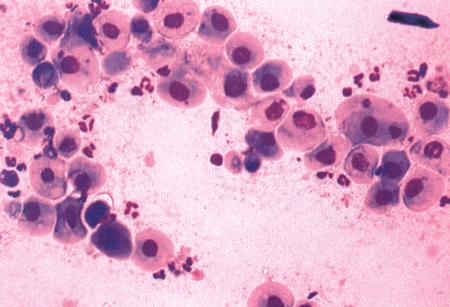

Фиг. 2.2.

Вагинальные выделения кошки (а). Выделения, типичные для фазы эструса. Большая часть клеток представляет собой безъядерные кератинизированные клетки или клетки с пикнотическим ядром. Присутствуют промежуточные клетки (b). Выделения, характерные для метэструса, — «течки», иногда наблюдаемой у кошек в конце эструса. Присутствуют поверхностные и промежуточные клетки, повышено содержание лейкоцитов. Этот короткий метэструс наблюдается в течение 24–48 часов (см. Приложение)